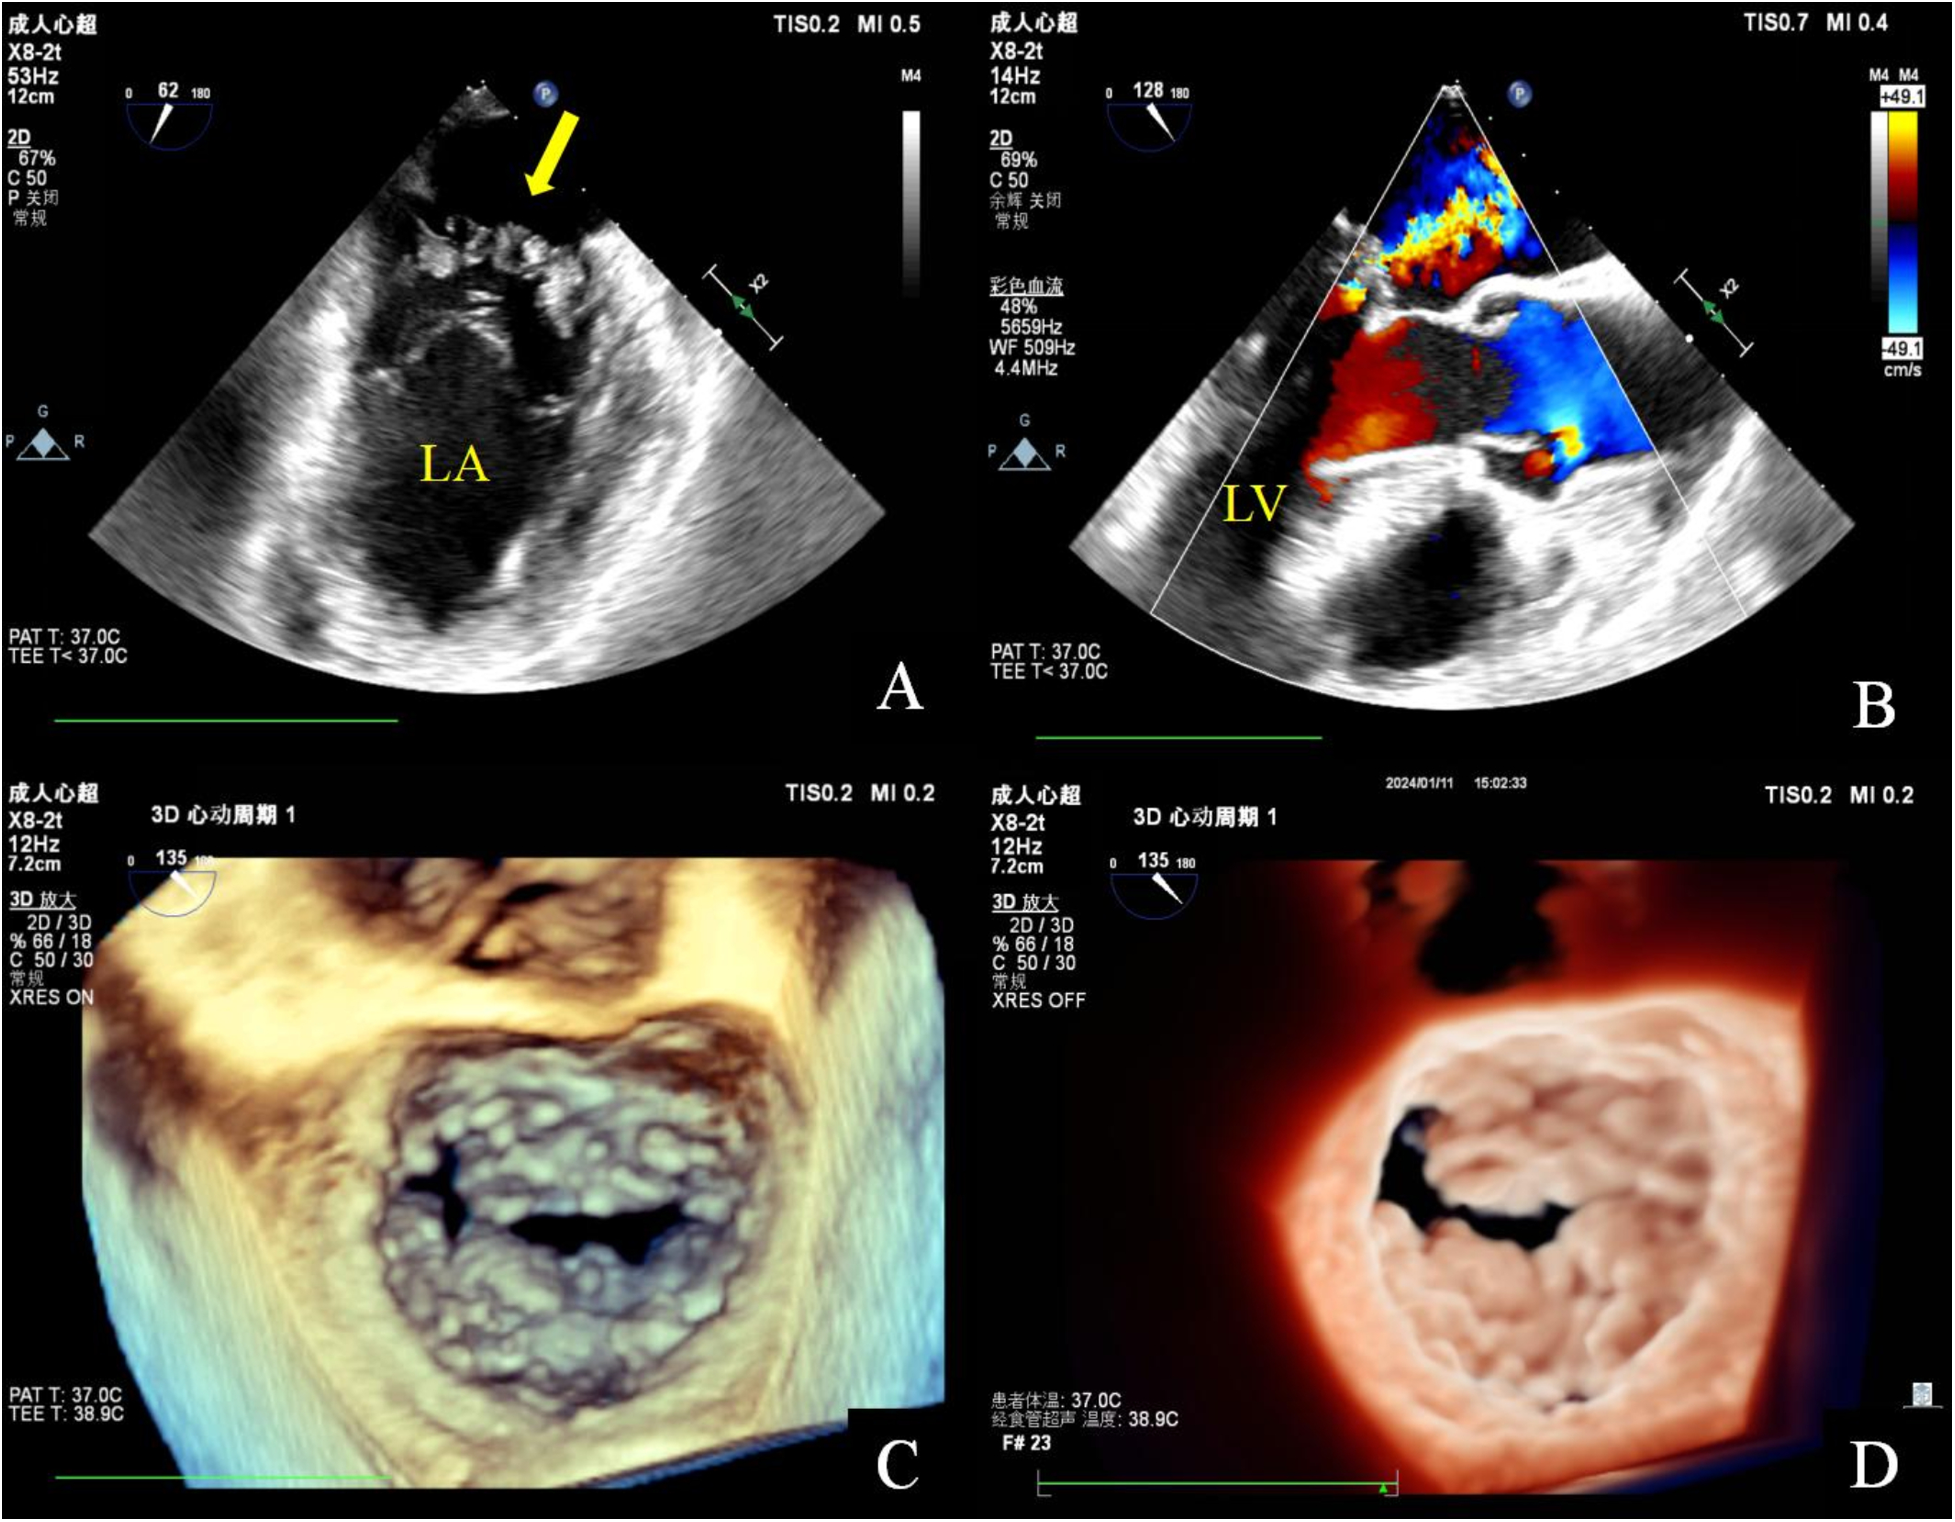

Figure 2

Transesophageal echocardiography. Mid-esophageal mitral commissural view: multiple irregularly shaped masses with a broad base attached to the anterior and posterior mitral leaflets. These masses are characterized by non-smooth surfaces, with an uneven internal echo (A). Mid-esophageal long axis view: color doppler flow imaging indicated that the lesion has a soft and deformable texture, leading to moderate mitral regurgitation (B). Three-dimensional transesophageal echocardiography: a diffuse distribution of granular additional echoes on the left atrial surface in two-thirds of the area of the anterior and posterior leaflets of the mitral valve, as well as the commissural cusps. The lesions merge with each other and are characterized by a wider base and a rough surface (C,D).

Two-dimensional transthoracic echocardiography (TTE) demonstrated left ventricular hypertrophy and left atrium enlargement. There were no segmental motion abnormalities. The patient’s left ventricular end-diastolic diameter (LVEDd) was 56 mm, his left ventricular end-systolic diameter (LVESd) was 40 mm, and his left ventricular ejection fraction (LVEF) was 57%. The anterior and posterior leaflets of the mitral valve were obviously thickened, especially on the edge area. Multiple iso-echoic neoplasms with irregular shapes were observed on the atrial sides of both the anterior and posterior mitral leaflets. The largest neoplasms were 14.6 mm × 12.0 mm on the anterior leaflet and 10.9 mm × 10.5 mm on the posterior leaflet, respectively (Figure 1). Color Doppler imaging showed moderate central mitral regurgitation (Supplementary Video S1). Laboratory tests showed no significant abnormalities in routine blood examination, coagulation, extractable nuclear antigen (ENA) antibody spectrum, liver function, and kidney function. Blood culture indicated no bacterial or anaerobic growth. A cranial CT scan suggested no signs of embolism in the brain. Computed tomography angiography (CTA) revealed the presence of calcified plaques on the thoracic and abdominal aortas, and also a lack of discernible indications of embolization. Infective and non-infective vegetations were ruled out based on these results. To further refine the neoplasm characterization, TEE was performed. TEE showed extensive thickening of the mitral valve, with multiple appendixes on the margins, with a smooth but irregular surface and a broad base attached to the anterior and posterior mitral leaflets (Figure 2). It seemed soft and deformed during valvular closure. Flickers could be seen with valve opening and closing, but without flail movement (Supplementary Video S2). Three-dimensional TEE revealed a diffuse distribution of granular neoplasms on the left atrial side of the mitral valve, especially two-thirds of the free edge area, as well as bilateral commissures. They were fused and the boundaries were unclear (Figure 2). The surface was cauliflower-shaped (Supplementary Video S3). There were no other valves involved in this case. Considering the risk of heart failure due to the valve disease and the risk of embolism, surgical treatment was performed. Intraoperative exploration showed that two-thirds of the area near the confluence margin of the anterior and posterior mitral leaflets were covered by diffuse tumor-like lesions. The commissural cusps and sub-valvular structures were involved as well, but there were no neoplasms on the left ventricular side of the leaflets. The lesions were merged with each other and characterized by a wider fundus and irregular shape. The granular structure partially extended toward the chordae tendineae. The impaired mitral valve was excised and submitted for histological examination and a microbiological culture. A prosthetic mechanical valve was replaced. An absence of bacterial proliferation was observed after a 48 h incubation for bacterial culture. The pathological examination showed a cauliflower-shaped protrusion approximately 2 cm × 1.5 cm × 1.2 cm in size on the excised mitral valve during the gross inspection (Figure 3). Under the light microscope, edema and mucinous degeneration were observed in the leaflet tissues, and there were spindle or stellate morphologic cells sparsely situated within an abundant mucinous matrix, which exhibited a mild morphology without abnormal nuclear division (Figure 3). The consultant pathologist suggested the diagnosis of a diffuse myxoma on the mitral valve with both leaflets, the commissural cusps, and the sub-valvular chordae tendineae extensively involved. The postoperative assessment indicated the prosthetic valve worked well (Table 1).